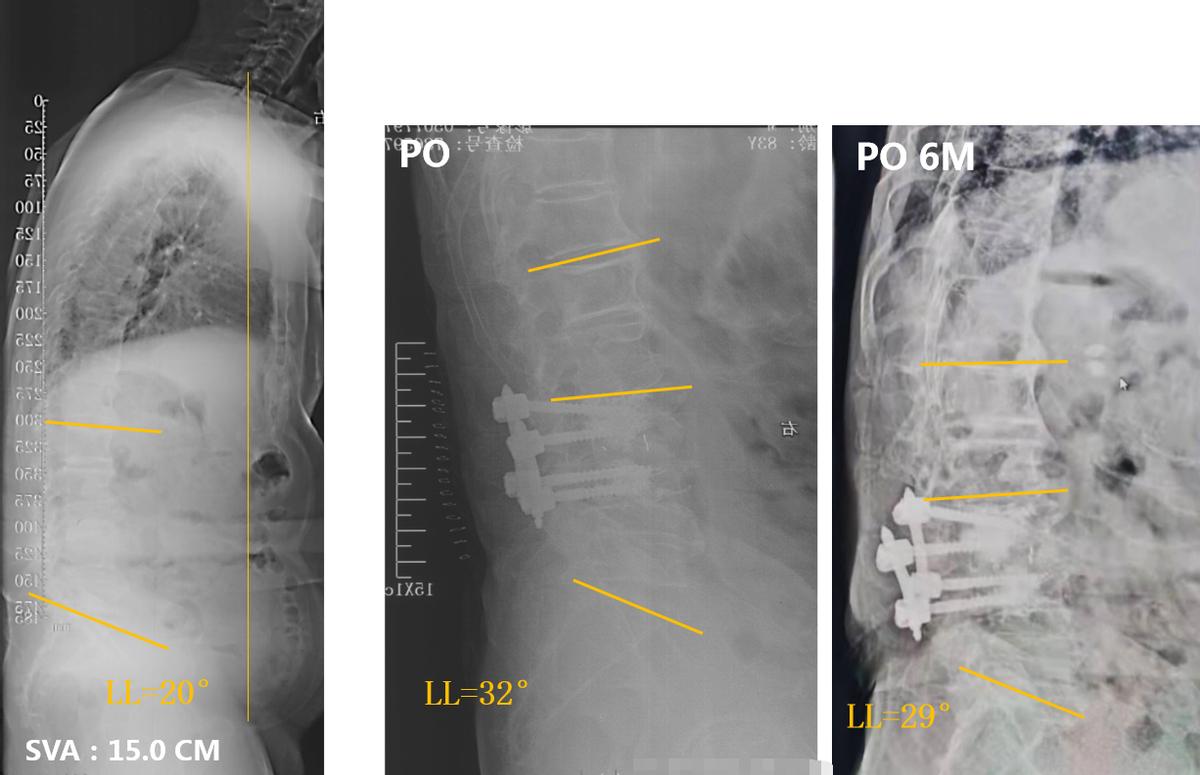

从患者的X线片可见,腰椎 35度右侧凸,顶椎L1/2。冠状位整体平衡还可以。矢状位:SVA 15.0CM。LL 20°。患者主诉病情加重前,无身体前倾等失平衡表现,腰痛引起异常体位。因此,我们判断患者的脊柱侧弯属于 Lenke-silvia III型 ADS。

由于患者Cobb角在30°左右,廖博主任团队决定进行“责任节段+X”短节段固定。为了精确责任节段,给患者进行了L5神经根选择性阻滞,原有症状没有诱发和缓解。因此,排除L4/5,将责任节段明确定位到L3/4。最终治疗方案决定为进行 L3/4的TLIF手术,钉道强化,L3椎体强化,术后进行长期的抗骨质疏松治疗。

术后影像学资料: